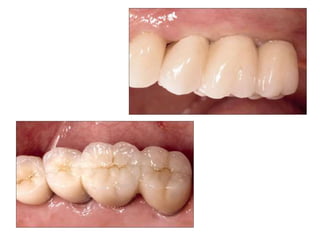

Implants require more precise impressions than crowns and bridges because implants lack a periodontal ligament to compensate for inaccuracies. It is critical to accurately record the three-dimensional position, angulation, and depth of implants to obtain a proper fitting definitive restoration. Making high quality impressions at the implant or abutment level is necessary to successfully fabricate implant prostheses.